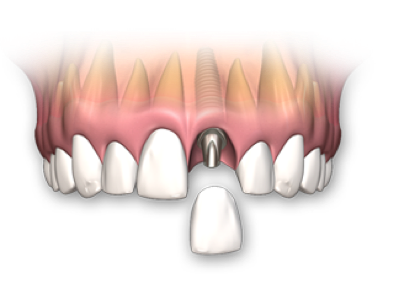

- (Si le falta un diente)

- Implante fabricado en Titanio Grado V de la más alta pureza.

- Reemplaza la raíz del diente y evita la perdida de hueso.

- Indicado para adultos y tercera edad.

- Respaldo casa de implantes SIN